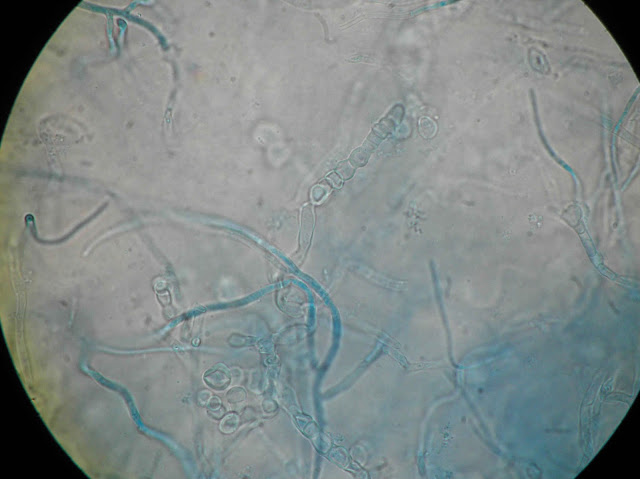

Ao exame microscópico observam hifas septadas de modo a apresentar artroconidios cilindricos ou elipsoides

| Repicagem com 6 dias de incubação. |